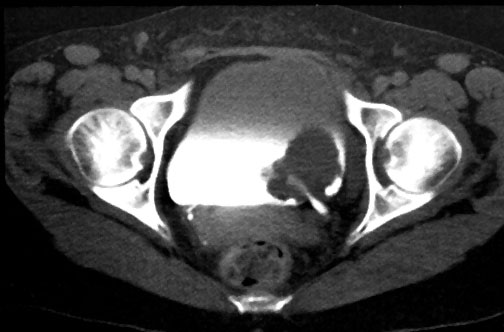

In the early years of BAUS, bladder cancer that was muscle-invasive at diagnosis (right) was typically treated by initial resection followed by external beam radiotherapy. Radiotherapy had been championed by the pioneering work of Clifford Morson, who would become the second President of BAUS in 1947.